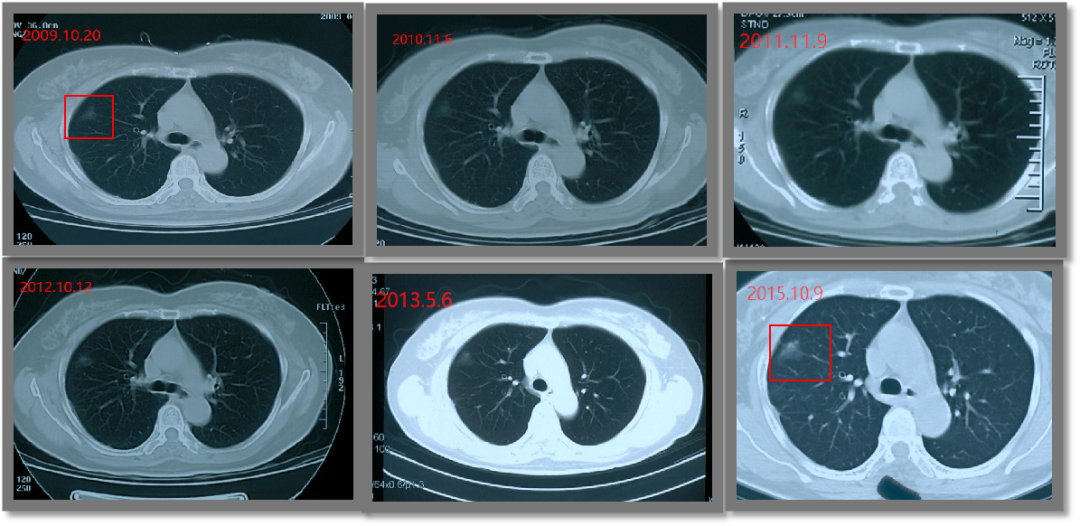

持久战!磨玻璃结节竟随访14年

2006年,张女士在一次偶然的体检中发现自己右肺上有个磨玻璃结节(GGO)。

由于之前因肾癌开过一刀,张女士内心极其排斥手术。于是在医生的建议下,决定先进行年度随访,等结节有变化了再做手术也不迟。

谁知道这一随访就是14年。

2016年,结节开始变大变实,并出现纤维化,由几个毫米增大到2公分以上。

而直到今年8月,结节才终于做微波消融打掉,并取到了满意的病理:原位腺癌。

14年的随访,对张女士的身体和精神来说,无疑都是一场持久战。和伴随自己十几年的结节终于告别后,她无比庆幸自己等到了微波消融微创治疗手段,心里的大石头落了地,再也不用提心吊胆过日子了!

图1 张女士随访期间的检查结果